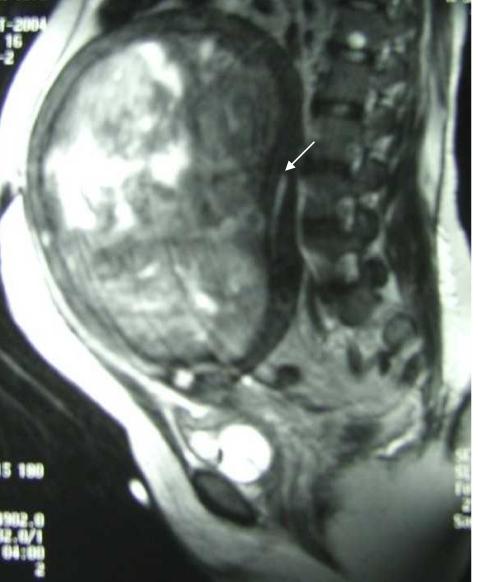

Fibroids are the commonest uterine neoplasms, occurring in 20% - 30% of women of reproductive age. In women who have pelvic masses of unknown cause, unusual manifestations of fibroids such as necrosis or degeneration may simulate a carcinoma or hydrometra resulting in problems with image interpretation. We report a case of an unsuspected large degenerated uterine fibroid in a lady mistakenly diagnosed as hydrometra on computed tomography scanning.